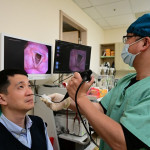

呂醫師說,患者剛來門診時,是由她先生推輪椅,把她推到床邊,她掙扎地爬到診療床上。呂醫師翻開患者背部看到五到八道疤痕,都是手術後留下的,疤痕硬的程度,用一般針灸幾乎刺不進去。像那種疤痕,僵硬也會造成疼痛,造成肌肉協調異常,這一部分是用針刀處理,因為一般的針已經刺不進去了。

患者因經絡能量比較低,此外肌肉存在一些肌痛點。分別使用針灸和雷射針灸處理。第三因患者因背部及髖關節引發骨架偏移,比如髖、骨盆、薦骨那邊,然後到腰椎、胸椎、肋骨有些偏差。用傷科的手法,把這些大偏差調得比較平順一點。

呂醫師指出,這名病人就是在針刀、針灸、雷射針灸、傷科手法四種方式的治療下,疼痛減輕不少,現在躺在床上可以翻身,可以站起來,可以走公園一圈。